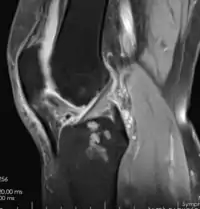

Resonancia magnética

Esta técnica en particular, se presenta como la técnica con mayor sensibilidad y especificidad en artrosis dado que muestra los tejidos blandos como el cartílago tanto como los tejidos óseos. Permite detectar cambios degenerativos precoces y complicaciones periarticulares y óseas, como la presencia de osteofitos, el adelgazamiento del cartílago hialino y edema subcondral, siendo particularmente útil cuando no hay certeza diagnóstica. Desgraciadamente, en el sector público no es muy utilizada debido a su alto costo y poca accesibilidad.[8]